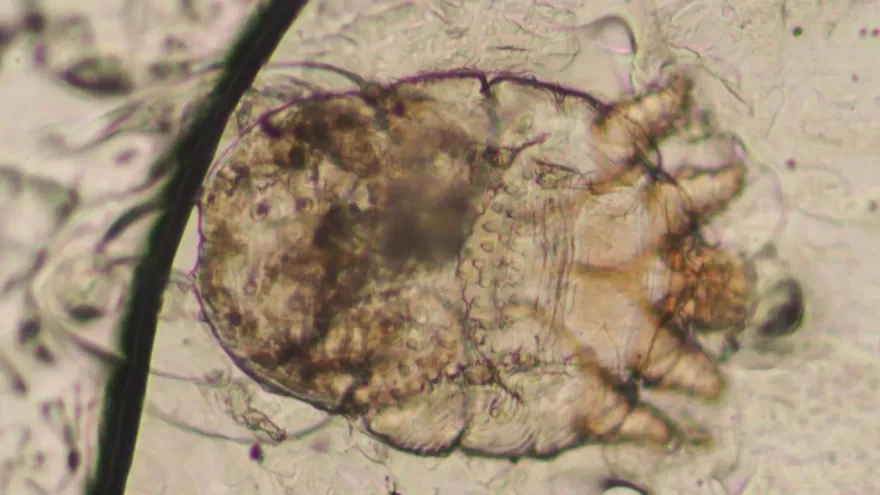

疥蟲

皮膚癢

抓癢

蟲咬

皮疹